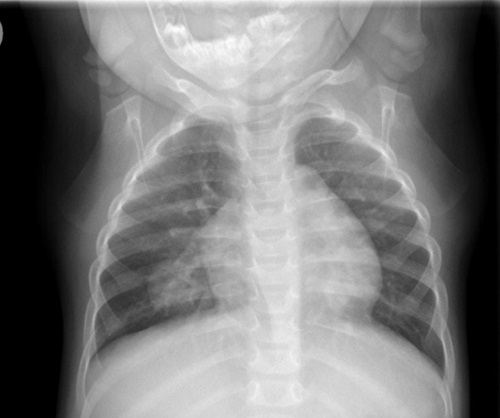

Ante la evolución tórpida de la imagen radiológica, se solicitó tomografía computarizada (TC) de tórax con contraste (Fig. 2) y angioTC, en el que se objetiva lesión en LID compatible con malformación vascular. Ante esta sospecha, se decide realizar angiografía (Fig. 3), donde se confirma el diagnóstico de malformación venosa pulmonar, no subsidiara de tratamiento intervencionista. Por este motivo, se decide iniciar tratamiento empírico con propanolol a 2 mg/kg/día. A los 6 meses se solicita TC de control, en el que se observa importante reducción de la malformación venosa. Al finalizar el tratamiento se realizó nuevo TC de tórax, en el que se objetiva la desaparición de la lesión focal de tipo vascular del LID.

Figura 2. Principales imágenes radiológicas del caso: TC pulmonar inicial